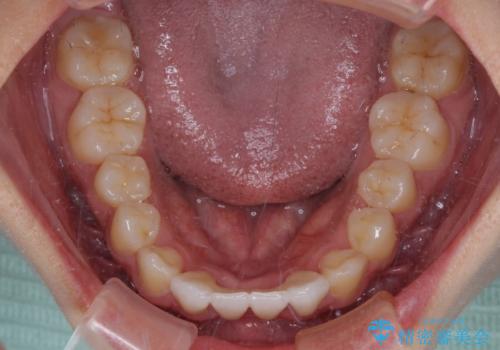

- 下顎前歯に乳歯が残っており、欠損もしていることを気にして来院された患者様です。

矯正治療終了後に速やかにオールセラミックブリッジを装着していくこととしました。